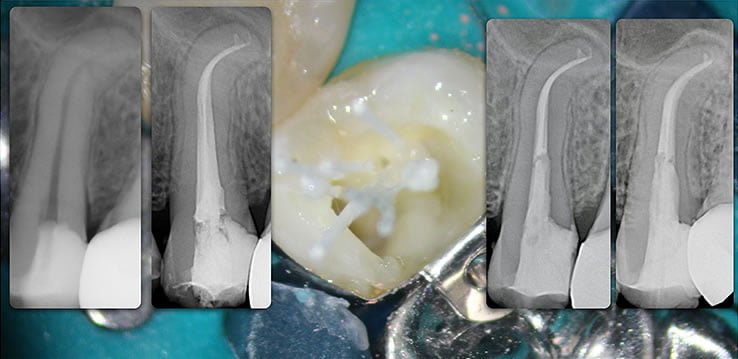

Template for x-rays

Biolight® DRILL-FREE posts are available in bundles of 4, 6, 9 and 12 strands. The post size is selected based on the width of the canal at the coronal area. Depending upon the canal width at the apical stop, a certain number of strands must be pushed to the stop. Both of the measurements are made with the assistance of a radiograph and the template that is included in the TRAINING KIT.